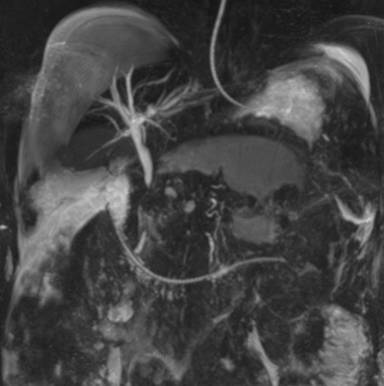

He was admitted into the intensive care unit, his oral hypoglycemic agents were discontinued and was initiated on insulin. A repeat CECT abdomen on the fifth day showed extensive pancreatic and peripancreatic necrosis (Figure 2). His hospital stay was complicated by worsening jaundice, a magnetic resonance cholangiopancreatography showed necrotic debris compressing on the common bile duct (Figure 3). He underwent a laparoscopic pancreatic necrosectomy with a laparoscopic cholecystectomy and placement of a feeding jejunostomy tube. Intra-operatively the gallbladder was found to be gangrenous with a friable biliary tract, and there was an avulsion of the cystic duct. On the ninth post-operative day he underwent an ERCP and stenting of the common bile duct. Further, his hospital course was complicated by methicillin resistant Staphylococcus Aureus infection in the central venous catheter which was treated with intravenous vancomycin. He was discharged from the hospital on the fiftieth day of hospital stay in a stable state. On follow up for 9 months post discharge, and on insulin for his diabetes, our patient is healthy and asymptomatic.

Figure 3. MRI abdomen on day 28 showing pancreatic necrosis compressing on the common bile duct. |